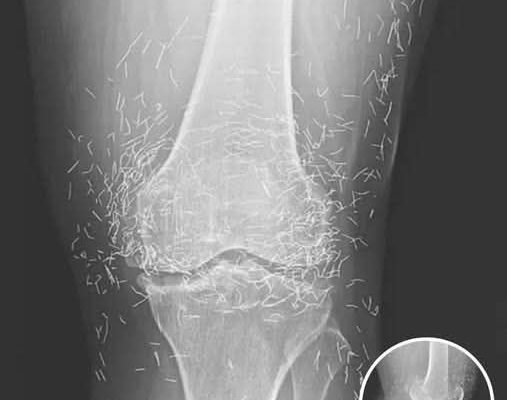

A 65-year-old woman in South Korea experienced a shocking medical discovery when doctors found hundreds of tiny gold needles embedded in her knee tissue during a routine X-ray. She had been suffering from chronic osteoarthritis, a condition that causes joint pain, stiffness, and inflammation due to cartilage breakdown.

In this case, the needles were intentionally left in her body as part of a long-term treatment strategy. Some practitioners believe that leaving gold needles or threads in place can provide ongoing stimulation to the affected area. However, medical professionals warn that this approach carries significant risks.

Dr. Ali Guermazi, a radiology expert from Boston University not involved in the case, explained that the human body can react negatively to foreign objects. Inflammatory responses, tissue damage, and infections are potential complications. Additionally, the embedded needles can interfere with medical imaging, making diagnosis more difficult.